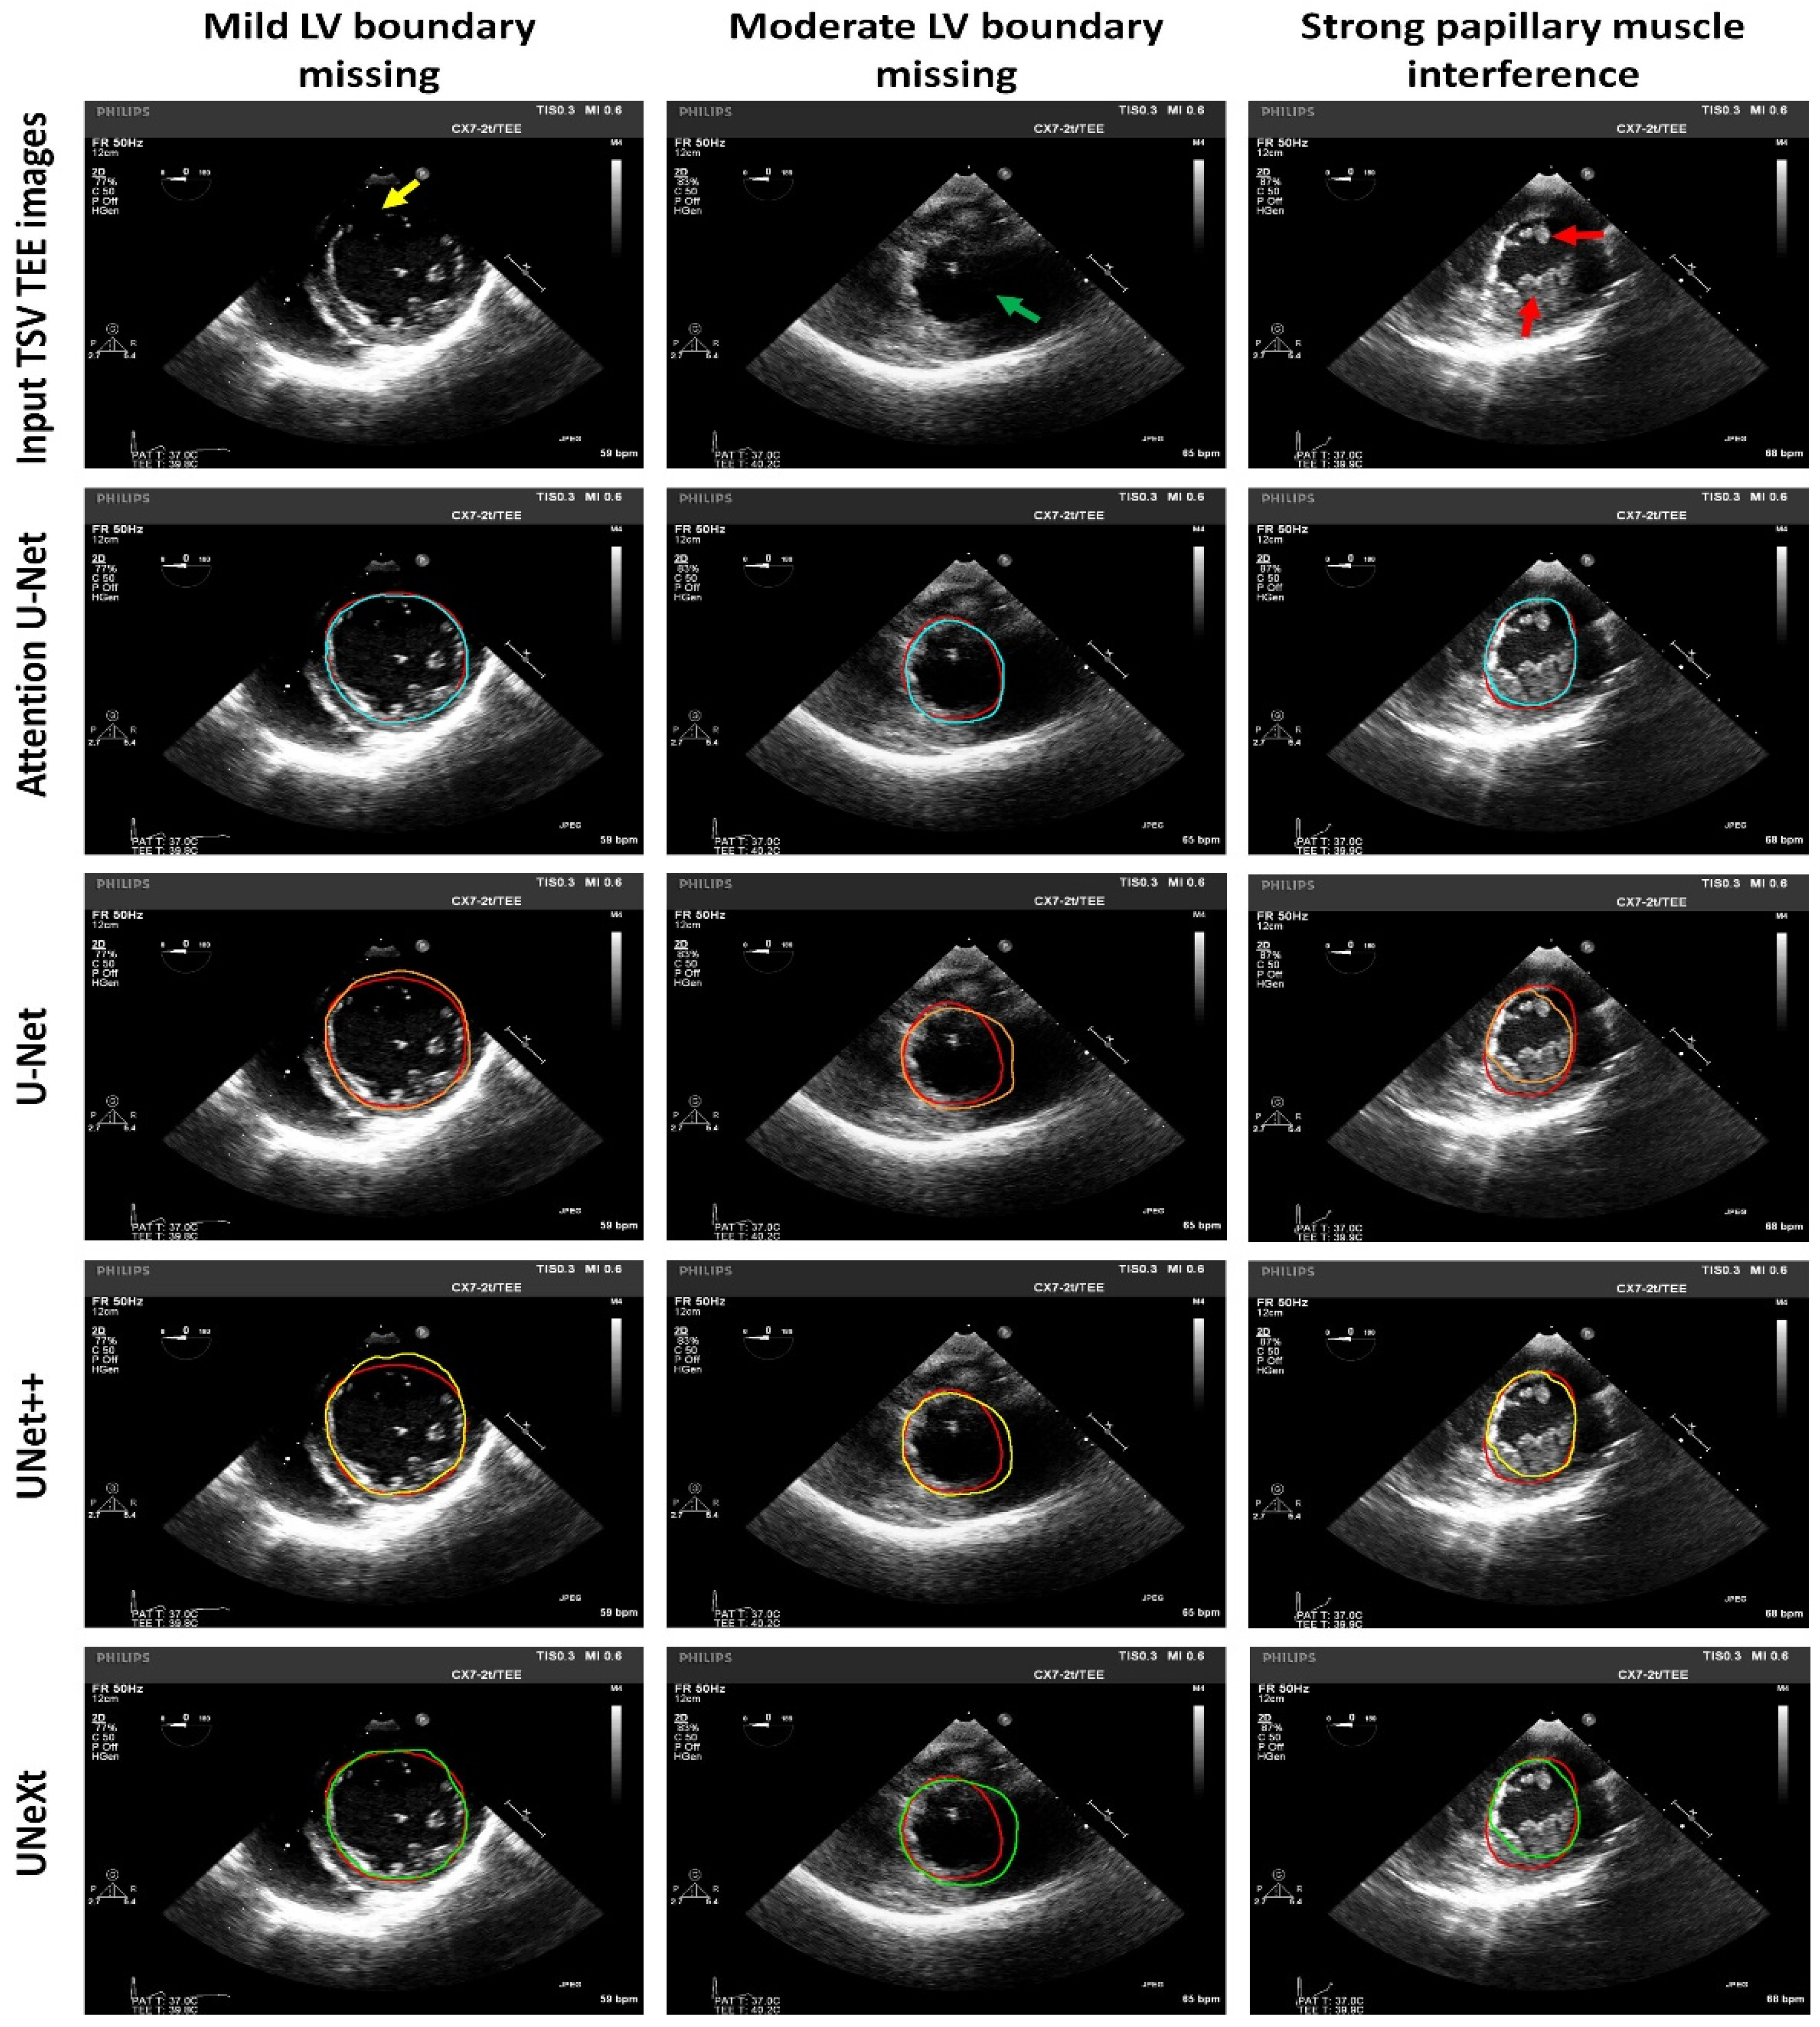

| Deep Learning Models | JSC (%) | DSC (%) |

|---|---|---|

| U-Net [18] | 84.71 ± 10.25 | 90.98 ± 7.19 |

| UNet++ [19] | 86.02 ± 8.70 | 91.76 ± 5.48 |

| UNeXt [20] | 84.20 ± 9.62 | 91.00 ± 6.23 |

| Attention U-Net [21] | 85.93 ± 8.71 | 92.00 ± 5.50 |